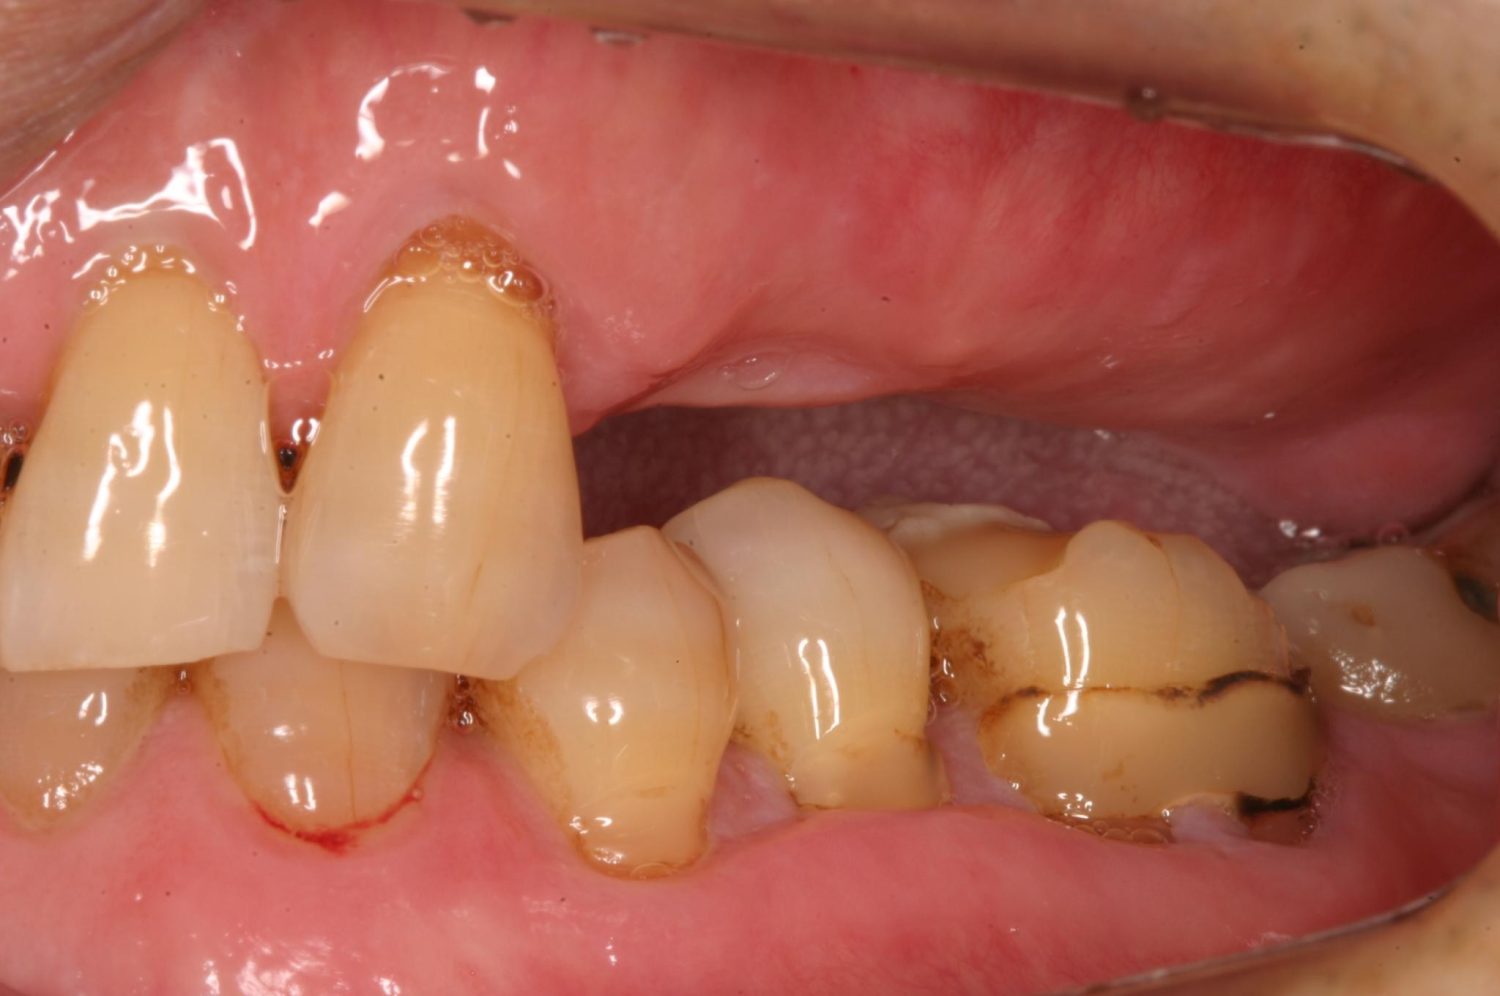

インプラント治療の症例紹介④

Before

After

主訴

義歯による疼痛

治療内容

下顎舌側に骨隆起があり義歯困難な状態。保存不可能な歯の抜歯を行い、インプラントを埋入し咬合再構成を行った。

治療費

2,851,200円(税込)

治療期間

29ヶ月

通院回数

26回

想定されたリスク

※咬合力の強い方なので、予防的にマウスピースの装着が必要。インプラント周囲炎の恐れがありました。

歯の欠損の対合歯の挺出等を修正し咬合平面を揃え咬合再構成を行った症例。